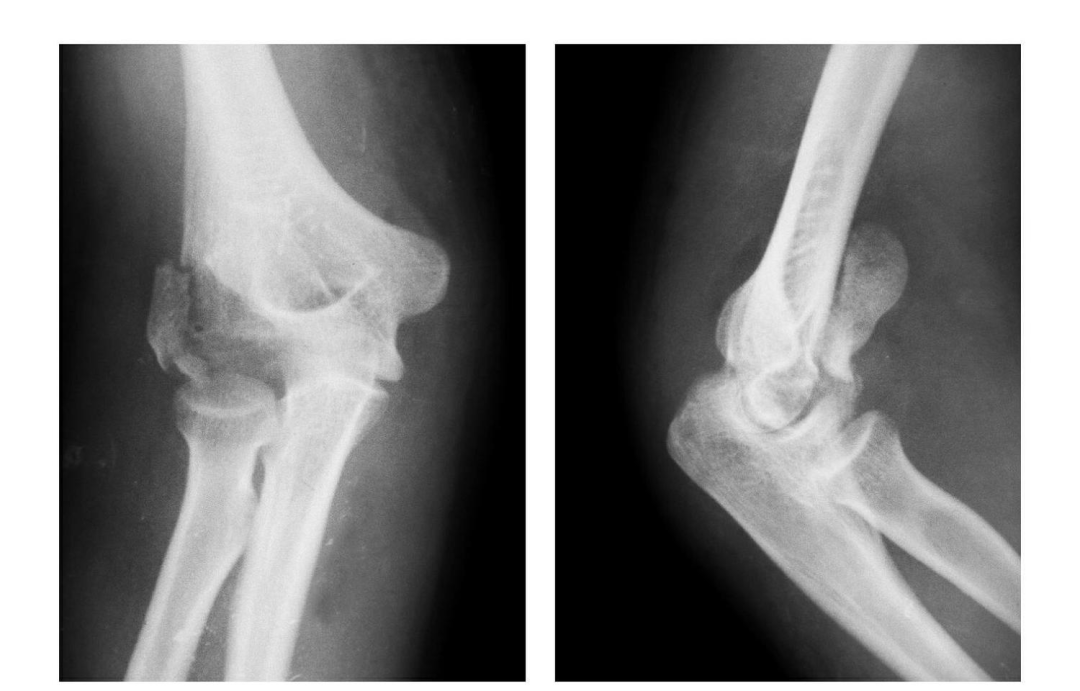

(7)Hahn-steinthal 骨折

全肱骨小头骨折,为一种少见的关节内骨折,多见于成年人。常由于跌倒时手过度伸直或在屈肘时因桡骨小头撞击肱骨小头,并同时有外翻力存在时发病,亦可伴有滑车骨折与内侧副韧带的撕裂。

例 1:肱骨小头基底部呈冠状面骨折,骨折块呈半球状向肘前上方移位。

例 2:肱骨小头基底部冠状面骨折,骨折块呈半球状向肘前移位并肱骨内上髁无移位骨折。

例 3:肱骨小头及滑车桡侧壁前半部呈整体性冠状面骨折,骨折块向前上移位并外髁骨折。